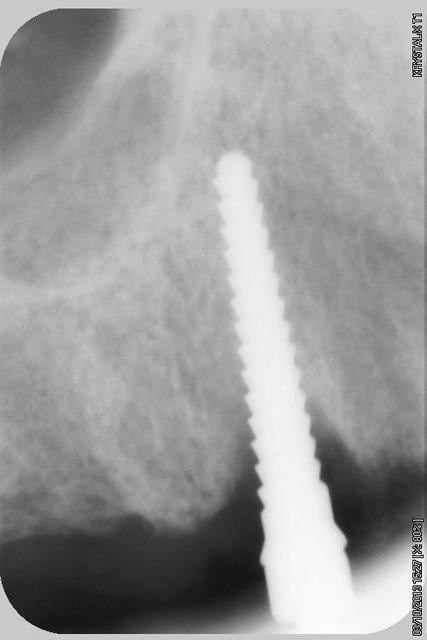

Puis 40120 en 15 avec léger SL, à l'ostéotome, et 40120 en 17.

Le pano est d'avant les extractions

quelques radios.

oui, bien sur ce sont des Tatum D1 en bas et D4 en haut